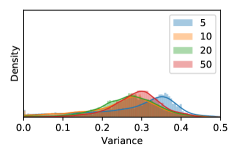

To model how different classifiers will respond to a given input , we assume that the prediction from classifier is sampled from a beta distribution that is characterized by two parameters by and . We further assume that is fixed to the same constant value for all ’s. Under this assumption, each input can be described by ( can be calculated since is fixed), easing further analysis. The Severity Level (SL) of the case represented by image can be characterized by the parameter . The larger the value of , the more severe the case of is. When and are close, the case is ambiguous as the distribution shifts towards being symmetric (i.e. signifying much disagreement among classifiers) rather than being one-sided (i.e. consensus among classifiers that is negative or positive). We provide a set of examples in Figure 2 and also Figure S.8 in the supplementary materials showing how the beta distribution can be used to capture diverse predictions given by an ensemble learner.

In contrast, the MC-dropout method showed the worst overall performance among the three, as it can be seen from the high ratios of SL0 examples among the uncertain negatives in Figure 4. The histograms in Figure 2 provides another perspective to look into the phenomenon, where a decent proportion of MC-dropout model’s predictions on SL0 inputs entailed low confidence (far from 0 or 1), which from another angle explained why MC-dropout was less specific in terms of lower FNP; many no-DR inputs (i.e. SL0) were erroneously assigned high uncertainty by MC-dropout models.